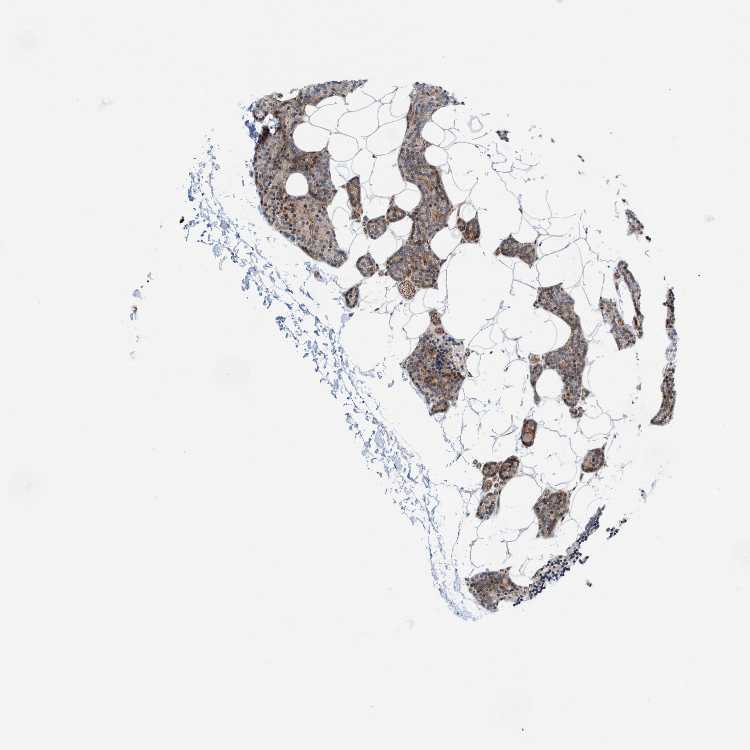

TISSUE PRIMARY DATA PARATHYROID GLAND Show tissue menu

Parathyroid gland

PARATHYROID GLAND - Expression summary

PARATHYROID GLAND - Antibody stainingi

Antibody staining in the annotated cell types in the current human tissue is reported as not detected, low, medium, or high, based on conventional immunohistochemistry profiling in selected tissues. This score is based on the combination of the staining intensity and fraction of stained cells.

Each image is clickable and will lead to virtual microscopy that enables deeper exploration of all samples and also displays staining intensity scores, fraction scores and subcellular localization as well as patient and tissue information for each sample.

Antibody HPA023501Antibody CAB005032Antibody CAB005039

Glandular cells Not detectedLowNot detected